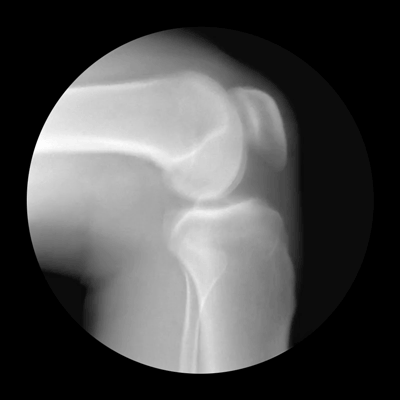

Knee